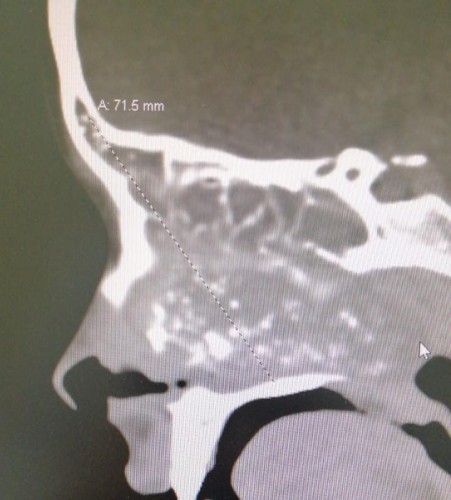

وأضافت بأنه بعد الفحوصات الطبية اتضح وجود ورم سرطاني على امتداد قاع الجمجمة ومتمدد في جميع الجيوب الأنفية وحتى البلعوم الأنفي.

وذكرت بأن الفريق الطبي قرر على الفور إجراء عملية جراحية استغرقت 4 ساعات تم خلالها استخدام تجهيزات متقدمة شملت جهاز الملاحة الجراحية والذي ساعد في تحديد المدى الجراحي أثناء العملية بناءً على الأشعة المقطعية والرنين المغناطيسي لاستئصال الورم الذي بلغ حجمه 9سم × 7سم × 5.8سم، تكللت العملية بالنجاح حيث تم استئصال الورم كاملاً بالمنظار عن طريق فتحة الأنف ودون أي جروح خارجية وإنهاء معاناة المريضة من الأعراض التي كانت تعاني منها.